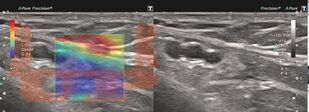

Учебное пособие содержит материал, характеризующий технологию ультразвуковой эластографии. Подробно описана методика проведения эластографии для печени и поверхностно расположенных органов. Представлены данные использования ультразвуковой эластографии в диагностических алгоритмах диффузных заболеваний печени, образований щитовидной и молочной желез с учетом клинических рекомендаций. Отдельное внимание уделено факторам, влияющим на результаты исследования. Представлен протокол эластографии сдвиговой волны печени. Приведены клинические примеры.